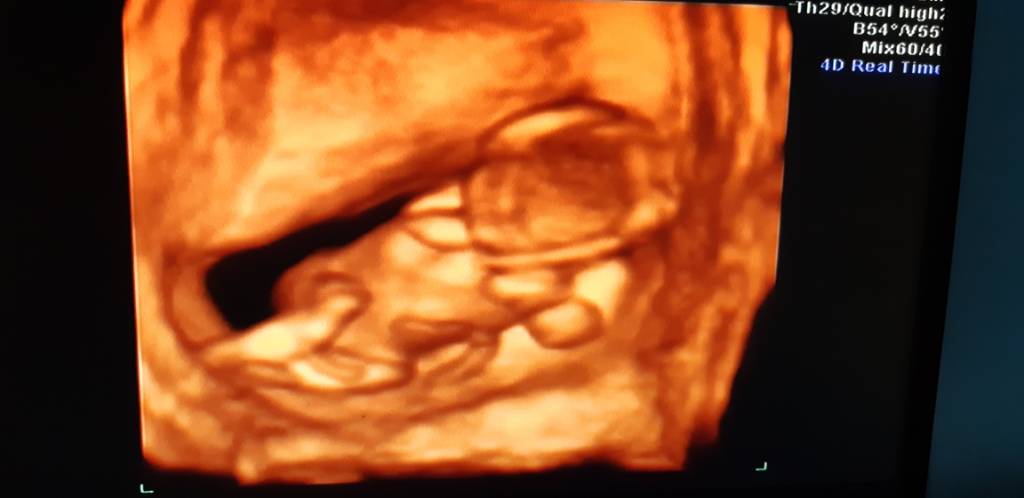

. My nie musieliśmy nic mówić, zadawać pytań, ponieważ lekarz był naprawdę konkretny i wyczerpująco opowiadał. Dziecko ma 6 cm, prawdopodobnie jest to córka, ale na tym etapie zdarzają się pomyłki, więc nie nakręcamy się. Pokazywał nam rączki, nóżki, kręgosłup, żołądek, pęcherz, serce. Prawie 160 uderzeń na minutę - musiałabym sprawdzić, bo nie pamiętam dokładnie czy 156 czy 159. Słyszeliśmy serduszko. Wyniki PAPPA będą za jakieś 2 tygodnie.

Zobacz załącznik 901374 Zobacz załącznik 901373